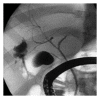

Bile leaks from the intrahepatic biliary tree are an important cause of morbidity following hepatic surgery and trauma. Despite reduction in mortality for hepatic surgery in the last 2 decades, bile leaks rates have not changed significantly. In addition to posted operative bile leaks, leaks may occur following drainage of liver abscess and tumor ablation. Most bile leaks from the intrahepatic biliary tree are transient and managed conservatively by drainage alone or endoscopic biliary decompression. Selected cases may require reoperation and enteric drainage or liver resection for management.